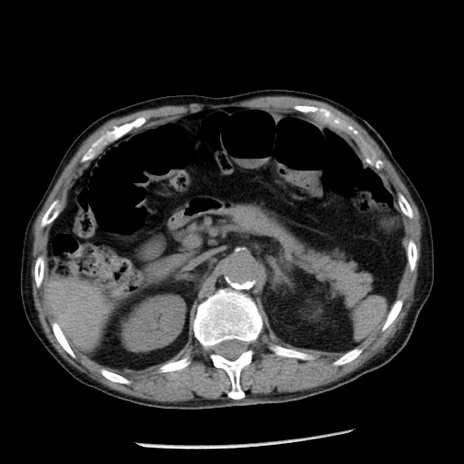

症例26(横断像)

【症例】80歳代男性

【主訴】嘔吐

【現病歴】昨晩2回嘔吐あり、今朝になっても嘔吐あり。来院。

【既往歴】胃潰瘍

【身体所見】意識清明、BT 37.6℃、BP 166/95mmHg、HR 100bpm、SpO2 97%、腹部:平坦・軟、腸蠕動音聴取良好、圧痛なし。

【データ】WBC 21900、CRP 1.46